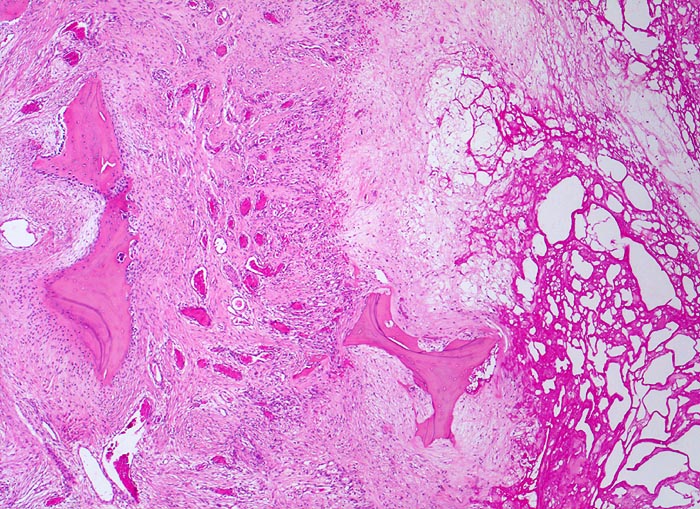

Randbereich einer Geröllzyste. Im Zentrum der Zyste nekrotischer Detritus und partiell resorbiertes avitales Knochenbälkchen. Die Geröllzyste wird umgeben von einem gefässreichen Granulationsgewebssaum. Darin liegt ein Knochenbälkchen, welches zystenwärts eine gesteigerte Resorption und auf der zystenabgewandten Seite einen gesteigerten Anbau mit Ausbildung einer Osteoblastentapete zeigt.

74-jährige leicht adipöse Patientin mit Anlaufschmerz, belastungsabhängigem Schmerz und zunehmender Versteifung im Hüftgelenk. Im Röntgenbild des Hüftgelenks zeigen sich eine Gelenkspaltverschmälerung, subchondrale Osteolysen, Usuren und randständige Osteophyten.